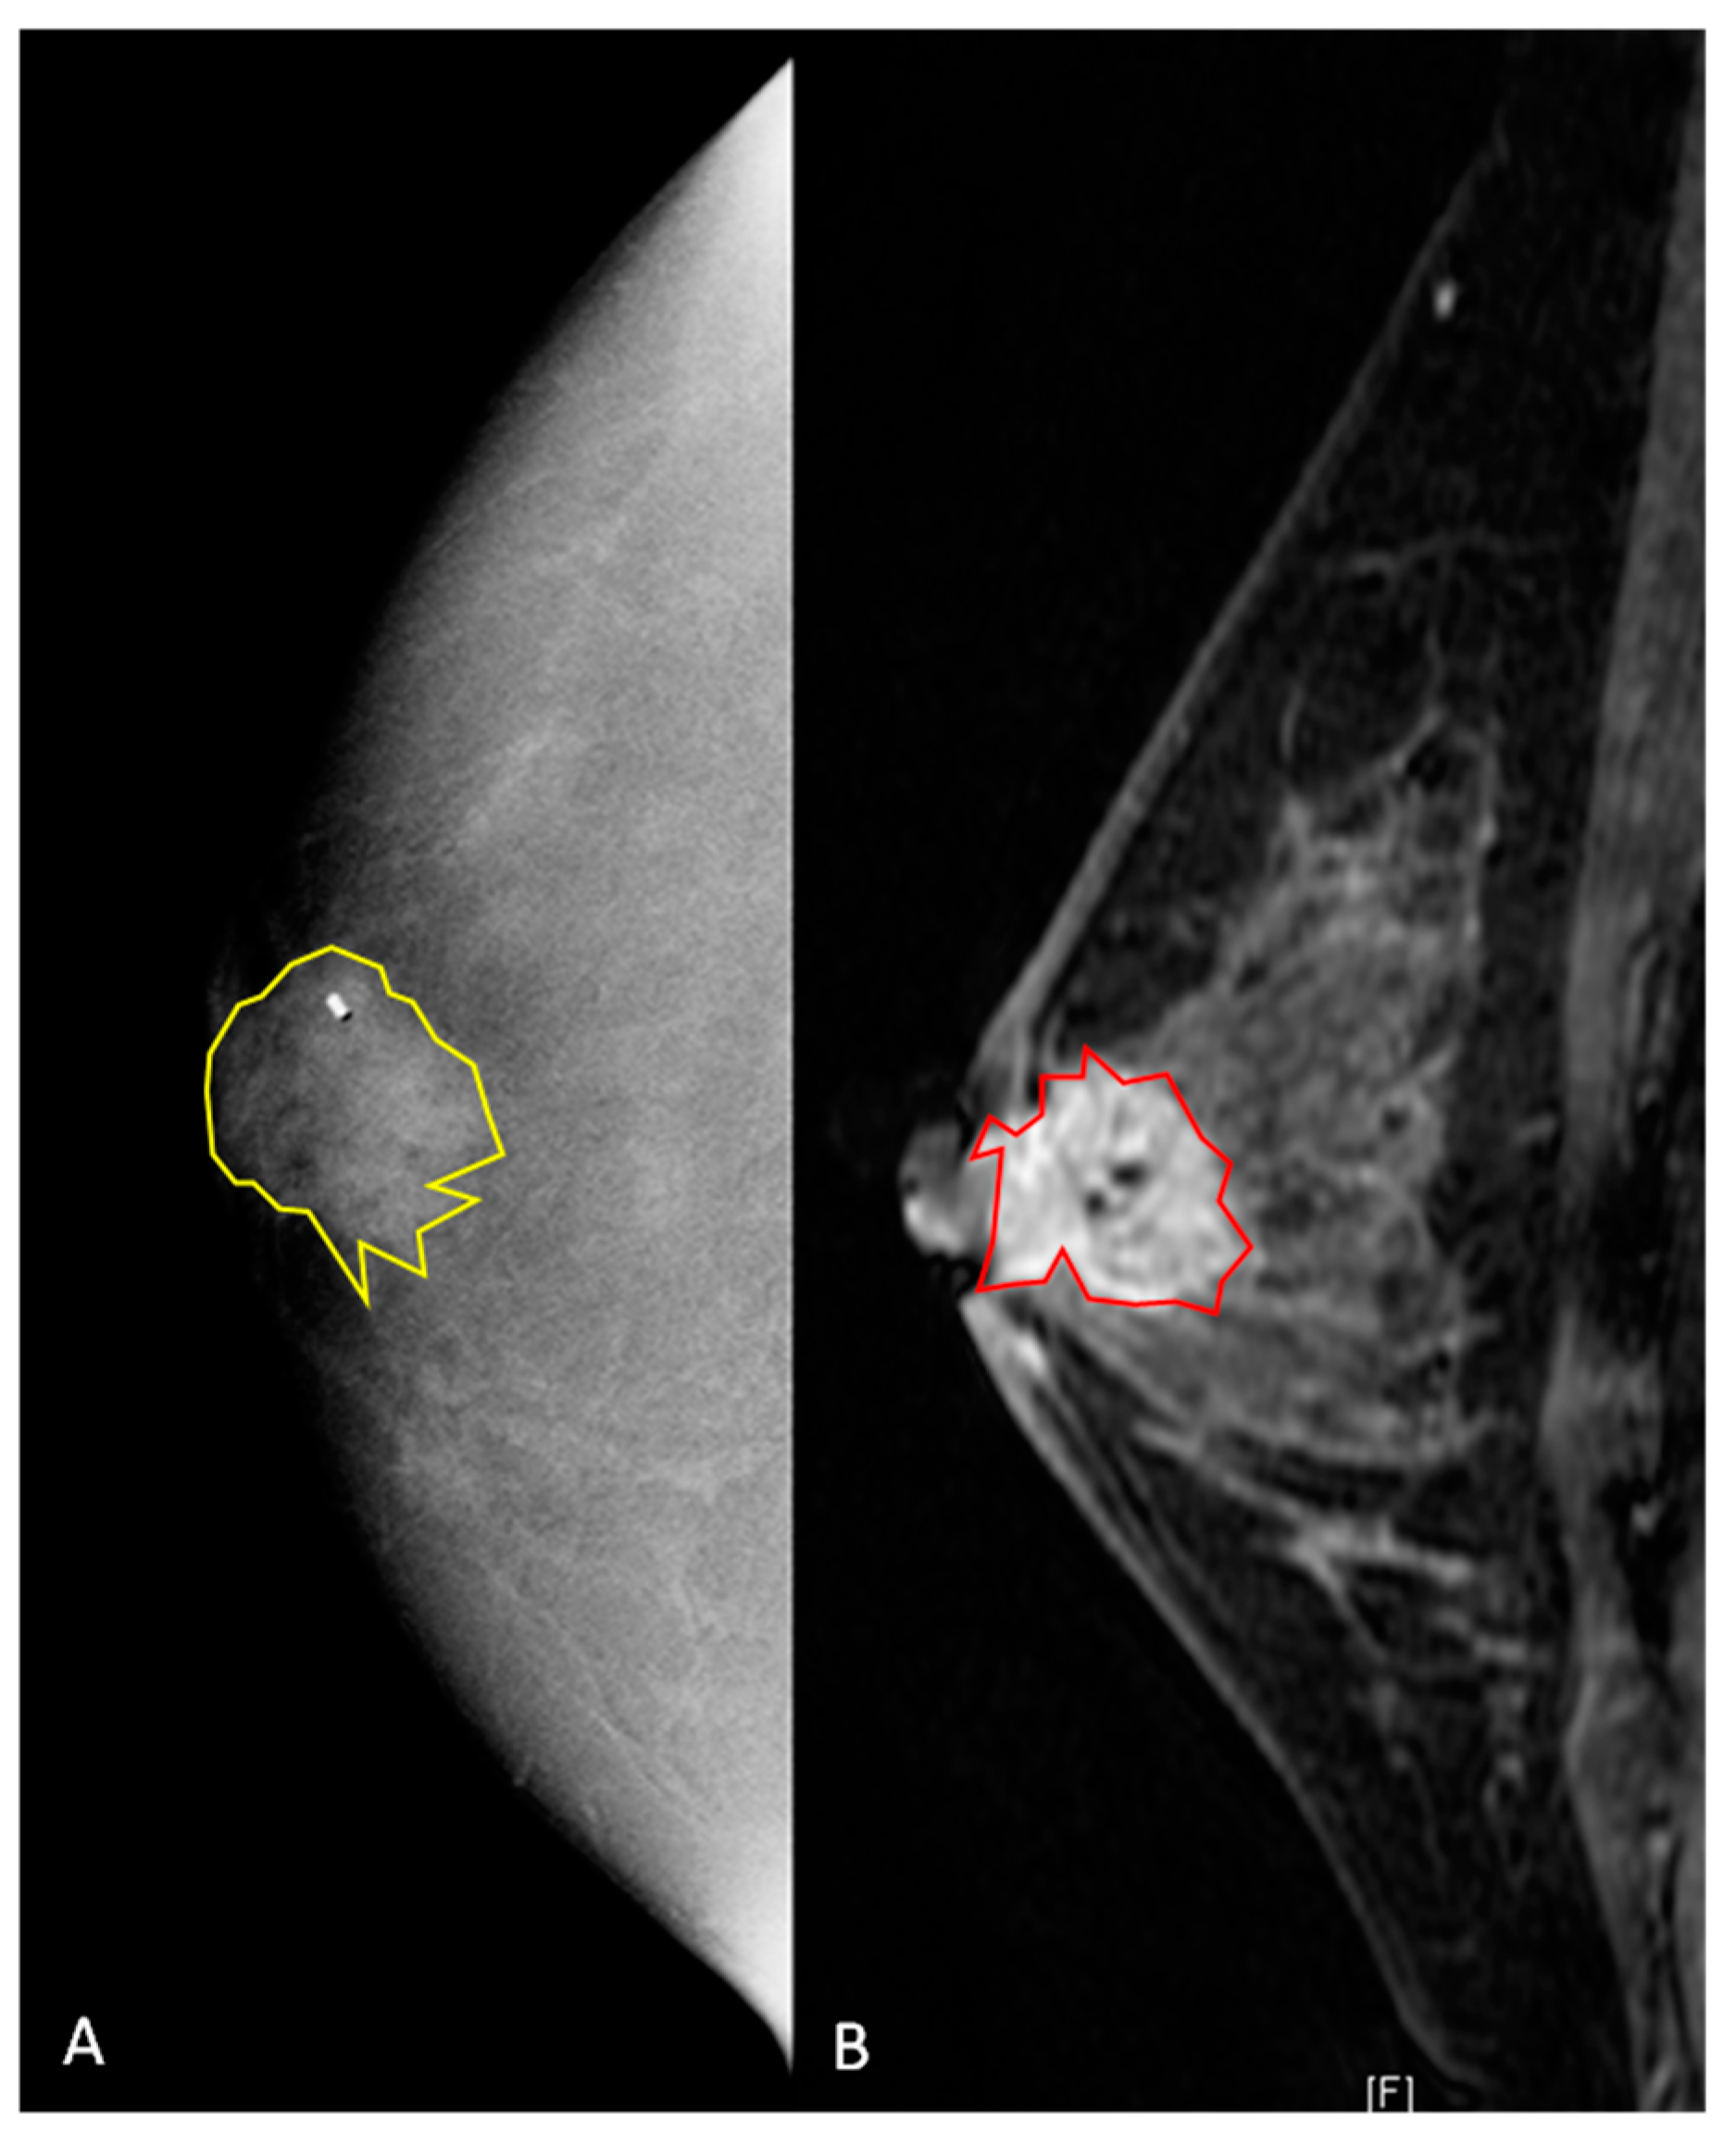

All DICOM (Digital Imaging and Communications in Medicine) images were transferred to a database and loaded into the open-source image processing tool OsiriX (OsiriX Foundation, Geneva, Switzerland). Lesion segmentation was performed on a per-patient basis, and in patients with multifocal disease, the lesion with the largest diameter was selected (Figure 2 and Figure 3). For texture analysis, a fellowship-trained radiologist with over 4 years of experience in breast imaging manually delineated the borders of the lesions for both CEM and DCE-MRI DICOM images, including all the enhancing parts of the index cancer, excluding foreign bodies (i.e., clips). For CEM DICOM images, the borders were delineated in either the CC or MLO view, depending on which view the tumor was most conspicuous. Radiomics analysis was performed by using MaZda software (Technical University of Lodz, Poland). Radiomic features were derived from the first-order histogram (HIS): co-occurrence matrix (COM), run-length matrix (RLM), absolute gradient (GRA), autoregressive model (ARM), the discrete Haar wavelet transform (WAV), and lesion geometry (GEO). In Supplementary Materials Table S1, all the specifics of the used radiomics features are listed. For further information about the radiomic features used, please refer to Szczypiński et al. [27].

Figure 3. A 42-year old women with a biopsy-proven invasive ductal carcinoma (G3, HR positive, HER2 negative) in the right retro-areolar space. (A) Contrast-enhanced mammography shows, on the right, a 22 mm rounded area of enhancement. The lesion was manually segmented (2D yellow region of interest), and the clip marker had to be included in the segmented area. (B) Sagittal fat-saturated post-contrast enhanced T1-weighted image. The breast is heterogeneously dense with moderate background enhancement. In the retroareolar right breast, there is a 22 mm spiculated mass containing a localizing clip from biopsy. The mass is inseparable from the nipple, which appears slightly retracted, and there is associated skin thickening. The lesion was manually segmented (2D red region of interest).